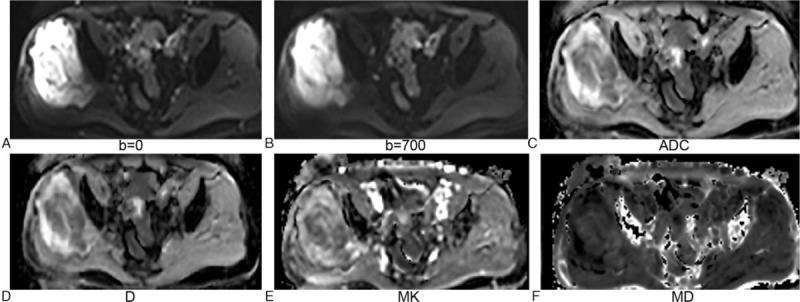

To investigate the feasibility of intravoxel incoherent motion (IVIM) diffusion-weighted imaging (DWI) and diffusion kurtosis imaging (DKI) in discriminating soft tissue sarcoma from vascular anomalies.Twenty-two patients with lower extremity soft tissue sarcoma and 15 patients with lower extremity vascular anomalies underwent IVIM-DWI and DKI. IVIM model generated true diffusion (D), perfusion fraction (f), and pseudo-diffusion coefficient (D). DKI model generated mean kurtosis (MK) and mean diffusion (MD). These parameters were measured by 2 radiologists separately through drawing region of interest. Intraclass correlation coefficient (ICC) was calculated to evaluate the inter-reader viability in measurement. The Mann-Whitney test was used to compare the parameters between vascular anomalies and soft tissue sarcoma. Receiver operating characteristic curves were constructed for assessing diagnostic accuracies.ICC was more than 0.8 for apparent diffusion coefficient (ADC), D, D, f, MK, and MD. Mean ADC, D, and MD were significantly lower in soft tissue sarcoma versus vascular anomalies (P < .05). Mean D and f were not significantly different (P > .05). Soft tissue sarcoma had significantly higher MK than vascular anomalies (P < .05). Areas under curve for ADC, D, MK, and MD were 0.876, 0.885, 0.894, and 0.812, respectively.IVIM and DKI are feasible in discriminating soft tissue sarcoma from vascular anomalies.